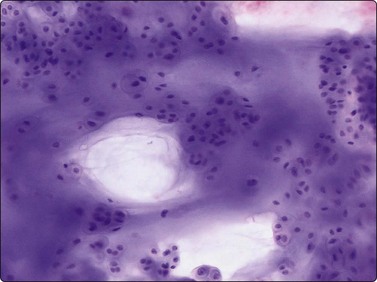

The cytological appearance of conventional ES is distinctive. Smears are generally highly cellular and are composed of both single cells and groups of loosely cohesive cells. The cells are fragile and naked nuclei as well as a faint gray–blue (MGG) background of detached cytoplasm are commonly seen. There is a characteristic mixture of two types of cells. One has abundant pale cytoplasm with vacuoles or large clear spaces, rounded or ovoid nuclei with finely granular chromatin and 1–3 small nucleoli (‘large light cells’). The other has scanty cytoplasm and irregular nuclei with dense chromatin (’small dark cells’). The two types of cells are most clearly distinguished within groups or clusters of cells, the small dark cells are interspersed, often as small molded groups, between large light cells (Fig. 16.31A). Rosette-like structures without a fibrillar center are occasionally present (Fig. 16.31B,C). The cytoplasmic vacuoles or clear spaces correspond to large deposits of glycogen (Fig. 16.31A).

image image image

Fig. 16.31 Ewing’s sarcoma

(A) A mixture of cells with larger pale-staining nuclei and cells with smaller and darker nuclei; note the cytoplasmic vacuoles and clear spaces in the pale cells (MGG, HP); (B,C) Rosette-like structure; nuclear chromatin and nucleoli more clearly seen in H&E than in MGG (A, H&E, HP; B, MGG, HP).